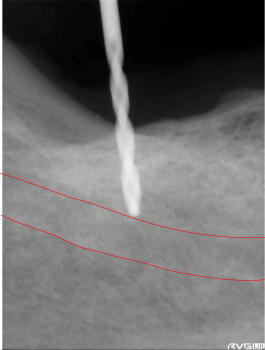

下歯槽管まで、近くなった所で安全性を確認するためレントゲン写真を撮影しまだ余裕があるのを確認します。 | ||

エミネオの本体を挿入します。下歯槽管までの安全性を確認します。まだ余裕があるいのが確認出来ます。 | ||